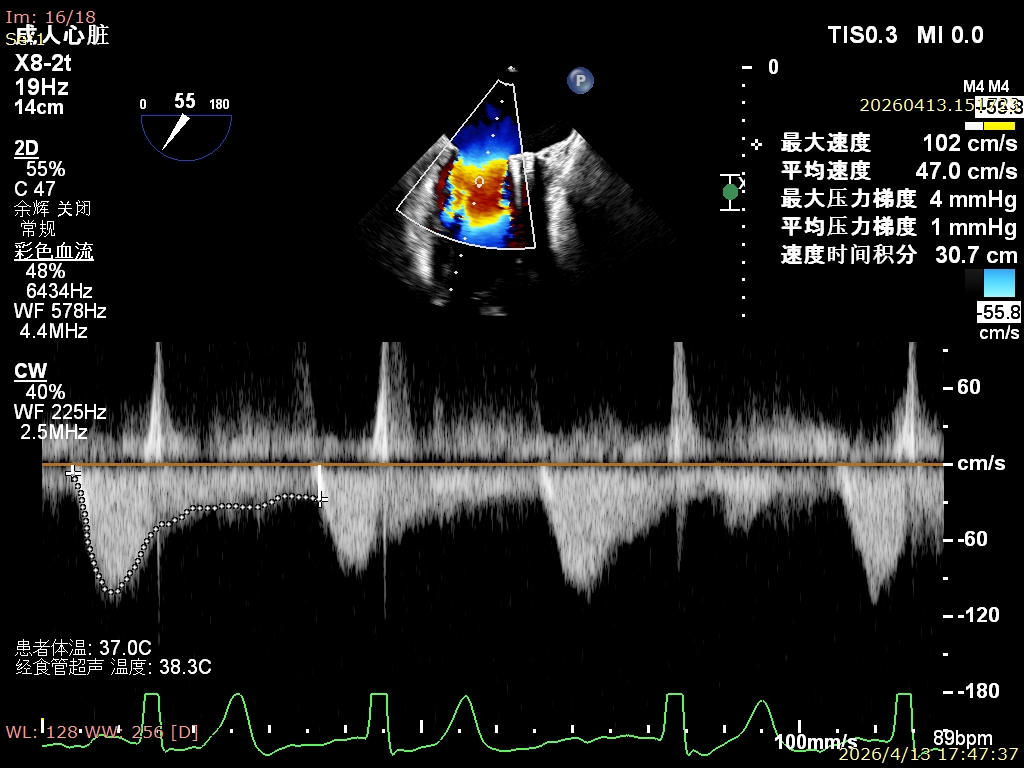

李晓峰教授团队行房间隔穿刺,高度为4.3cm,随后顺利置入导引鞘及SW0609(短宽型)二尖瓣夹,先于外交界区进行夹合,由于瓣叶活动度较大且瓣环存在扩张,李晓峰教授采用“反向捕获”技术成功捕捞瓣叶,释放后内侧仍残余部分脱垂及反流,决定于内侧补一枚XW0612(长宽型)二尖瓣夹。术后即刻评估显示,患者二尖瓣反流从重度降至轻量,平均跨瓣压差仅为1mmHg,肺静脉逆流征象得到显著改善,手术取得圆满成功。